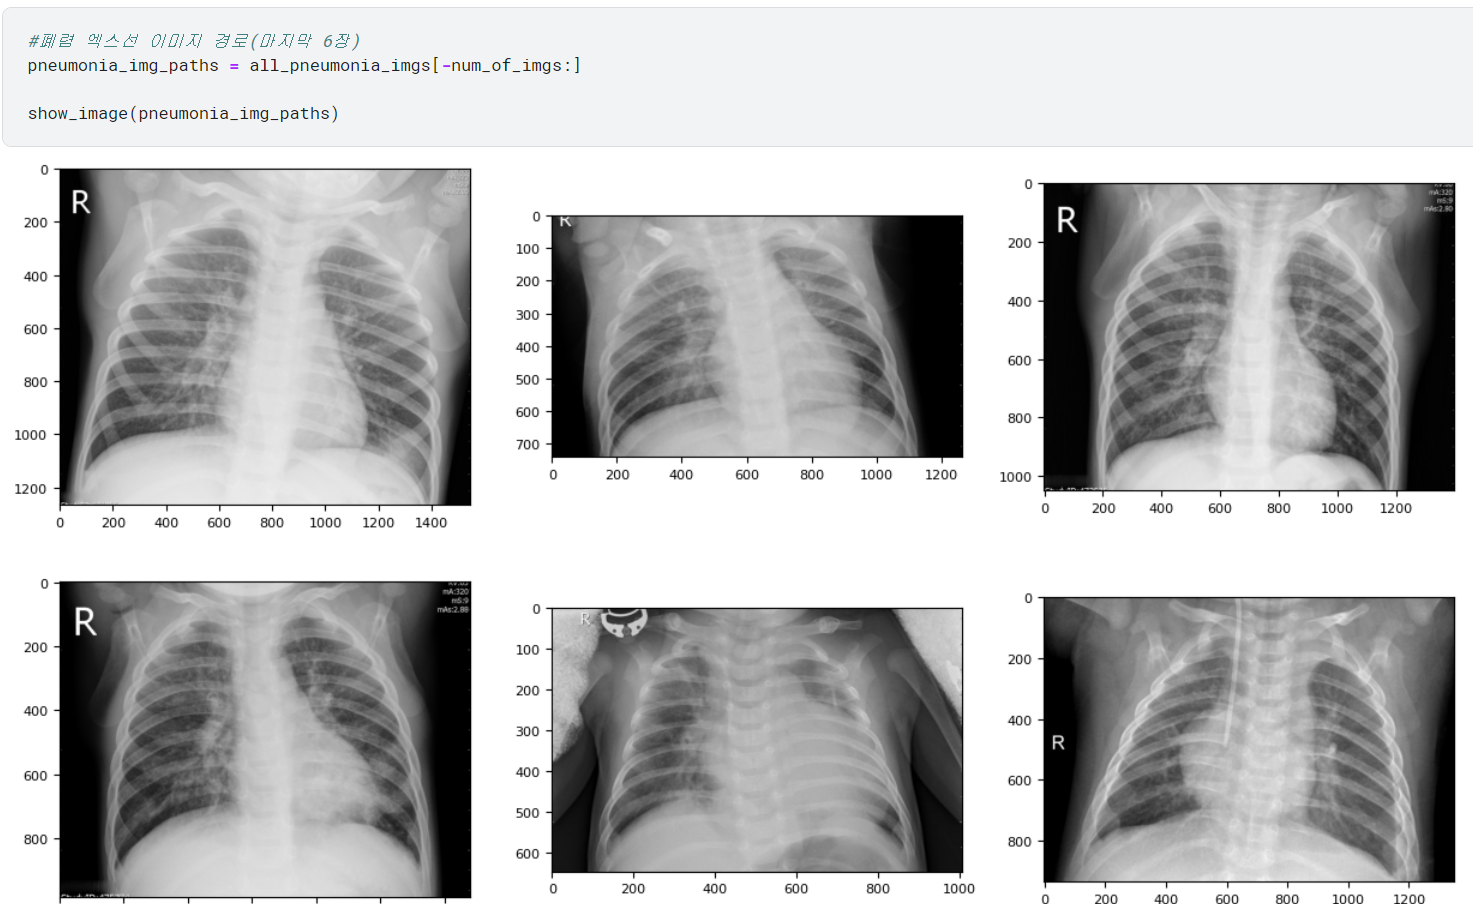

♣ 데이터 시각화